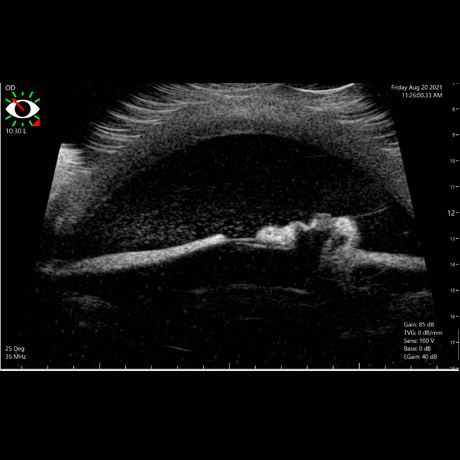

Na Oftalvet dispomos de equipamento avançado, de última geração, que permitem o diagnóstico das mais variadas doenças que afectam o globo ocular e seus anexos.